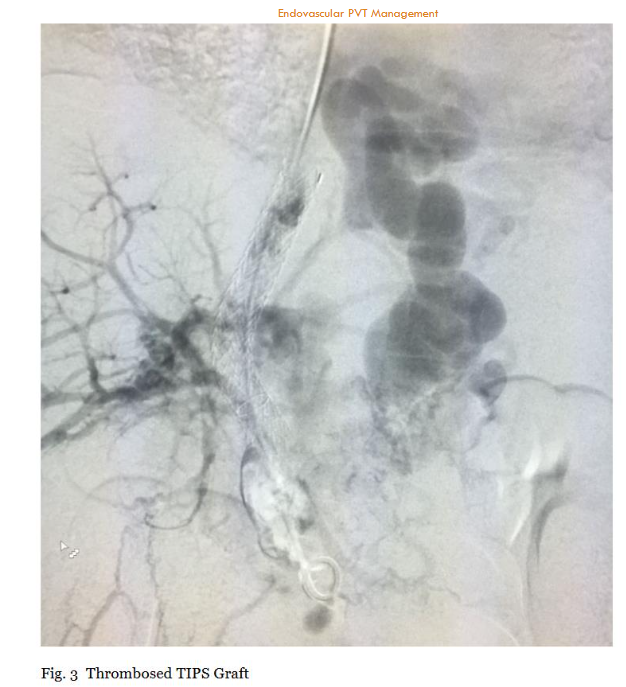

Portal vein thrombosis (PVT) is a clinically significant and anatomically complex vascular disorder characterized by the formation and progressive growth of thrombi within the portal venous system, notably affecting the main portal vein, superior mesenteric vein (SMV), and splenic vein. The incidence of PVT is estimated at 2 to 4 cases per 100,000 people in the general population, though it rises substantially to approximately 11% over 5 years in patients with cirrhosis, where it is strongly associated with advanced portal hypertension and increased mortality. The etiology of PVT is multifactorial, commonly associated with liver cirrhosis, hepatocellular carcinoma, myeloproliferative disorders, coagulation abnormalities, inflammatory diseases, and abdominal infections. These pathological conditions predispose patients to hypercoagulability, endothelial dysfunction, and altered hemodynamics, thereby facilitating thrombus formation. Inherited prothrombotic states, such as factor V Leiden mutation or protein C/S deficiency and acquired factors like malignancy or recent abdominal surgery further exacerbate the risk. The clinical manifestation of PVT varies considerably, ranging from asymptomatic presentations discovered incidentally through imaging, to severe complications including acute abdominal pain, intestinal ischemia, variceal hemorrhage, ascites, splenomegaly, and liver failure. Acute PVT, defined as symptom onset within days to weeks, often presents with sudden abdominal pain and may lead to bowel infarction if mesenteric involvement is extensive, carrying a mortality rate of up to 20%-30% without prompt intervention. Chronic PVT, in contrast, allows for collateral vessel formation (cavernous transformation), which mitigates acute ischemia but contributes to long-term portal hypertension and its sequelae. Diagnosis typically relies on Doppler ultrasound as the initial modality, with computed tomography (CT) or magnetic resonance imaging (MRI) providing detailed assessment of thrombus extent, chronicity, and exclusion of malignancy, such as hepatocellular carcinoma invading the portal vein. The management of PVT, especially acute and extensive thrombosis, remains challenging due to the intricate balance required between effective thrombus clearance and the risks associated with invasive interventions. Standard therapeutic management primarily relies on systemic anticoagulation, typically involving low molecular weight heparin transitioned to oral anticoagulants like vitamin K antagonists or direct oral anticoagulants (DOACs). While anticoagulation therapy is effective in preventing further thrombus propagation and achieving partial recanalization in up to 40%-60% of cases, it frequently proves insufficient in resolving established and extensive thromboses, particularly those presenting acutely with complete vessel occlusion. The limitations of anticoagulants are exacerbated by factors such as the chronicity of thrombus, clot organization, vessel wall adherence, and the anatomical complexity of affected venous territories. Moreover, in patients with cirrhosis, anticoagulation must be balanced against bleeding risks from varices or coagulopathy. Additional complexities arise in managing thrombosed trans jugular intrahepatic portosystemic shunt (TIPS) grafts. TIPS is a critical interventional procedure used to manage portal hypertension, but its long-term patency can be compromised by thrombotic occlusion in up to 20%-50% of cases within the first year. The thrombus within TIPS grafts tends to be highly organized, dense, and resistant to conventional treatments, posing significant technical difficulties for reintervention, including challenging access through previously placed stents and shunts, the risk of vessel perforation, and managing peri-procedural bleeding risks. Clot morphology significantly influences treatment strategies for PVT and thrombosed TIPS grafts. Acute thrombi, characterized by their relatively soft and fibrin-rich composition, are more responsive to thrombolytic therapies and mechanical thrombectomy techniques. Conversely, chronic thrombi, characterized by fibrosis, collagen deposition, and vessel adherence, require more aggressive and mechanically disruptive approaches. The differentiation between acute and chronic thrombi through imaging and clinical assessment is therefore crucial for therapeutic planning and prognosis. Percutaneous transhepatic and trans jugular approaches to accessing the portal venous system carry inherent procedural risks, including inadvertent liver injury, bleeding complications, vessel perforation, and potential embolization. These risks necessitate detailed pre-procedural planning, operator proficiency, and advanced imaging modalities to ensure procedural safety and effectiveness. Recent advancements in endovascular techniques have introduced the use of large-bore thrombo-aspiration catheters in combination with rotational morcellation as promising alternatives to traditional therapies. These innovative mechanical thrombectomy methods facilitate rapid removal of extensive thrombus volumes by aspirating fragmented thrombus material and simultaneously disrupting organized clots through rotational morcellation. This combination approach potentially reduces procedure times, enhances thrombus clearance rates, and improves clinical outcomes, particularly in cases refractory to anticoagulation alone. This manuscript provides an analysis of five clinical cases utilizing an 18 French thrombo-aspiration catheter combined with rotational morcellation in patients with acute and sub-acute portal venous thrombosis and thrombosed TIPS grafts. By assessing procedural outcomes, technical considerations, and safety profiles, we aim to determine the efficacy and clinical utility of this differentiated endovascular approach, offering valuable insights into its potential role in overcoming existing treatment challenges.

2.3.1. Initial Access, Portal Venography, and TIPS Exploration

Initial access was obtained through the right internal jugular vein under ultrasound guidance to minimize complications, followed by advancement of a 0.035-inch guidewire and 8-10 Fr sheath through pre-existing TIPS grafts. Upon reaching the portal venous system, diagnostic portal venography was performed using 10-20 mL iodinated contrast at 5 mL/s. Imaging delineated thrombus extent, morphology (e.g., occlusive vs. non-occlusive), and chronicity, with comparison to pre-procedural CT/MRI for correlation. TIPS exploration under fluoroscopy confirmed graft patency, excluding stenosis (>50% diameter reduction) that could alter strategy. This step was critical to quantify baseline thrombus burden (percentage occlusion via digital subtraction angiography) and guide device positioning, ensuring efficacy documentation through pre-intervention metrics.

Persistent sub-acute thrombus (denser, resistant) was assessed fluoroscopically. The guidewire was withdrawn, and a 135 cm CLEANER 15™ rotational morcellation catheter was inserted through the CLEANER Vac lumen, positioned at the thrombus site in TIPS and portal segments. Morcellation at 4000 RPM fragmented clots into aspiratable particles. Intermittent contrast injections monitored progress, avoiding vessel/stent injury. Concurrent pulsed aspiration removed debris, repeated until >85% clearance (restored patency on venography). Final imaging confirmed improved flow with minimal residual (<15%). This sequential method was chosen for its synergy: morcellation disrupts organized clot (ineffective with aspiration alone), while aspiration prevents embolization, supported by case series showing high success rates in similar venous thromboses. Efficacy was documented via immediate post-procedure venography (thrombus reduction %), procedure time, blood loss, and absence of complications.